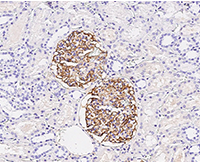

Immunochemical staining of human CD35 in human kidney.

Immunochemical staining of human CD35 in human kidney. Image Credit: Sino Biological Inc.